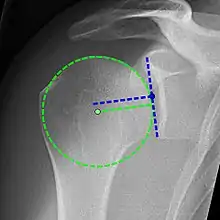

Xray

X-ray projectional radiography cannot directly reveal tears of the rotator cuff, a 'soft tissue', and consequently, normal X-rays cannot exclude a damaged cuff. However, indirect evidence of pathology may be seen in instances where one or more of the tendons have undergone degenerative calcification (calcific tendinitis). The humeral head may migrate upwards (high-riding humeral head) secondary to tears of the infraspinatus, or combined tears of the supraspinatus and infraspinatus.[46] The migration can be measured by the distance between:

- A line crossing the center of a line between the superior and inferior rims of the glenoid articular surface (blue in image).

- The center of a "best-fit" circle positioned over the humeral articular surface (green in image)

Normally, the former is positioned inferiorly to the latter, and a reversal is therefore indicating a rotator cuff tear.[46] Prolonged contact between a high-riding humeral head and the acromion above it, may lead to X-rays findings of wear on the humeral head and acromion and secondary degenerative arthritis of the glenohumeral joint (the ball and socket joint of the shoulder), called cuff arthropathy, may follow.[45] Incidental X-ray findings of bone spurs at the adjacent acromioclavicular joint may show a bone spur growing from the outer edge of the clavicle downwards towards the rotator cuff. Spurs may also be seen on the underside of the acromion, once thought to cause direct fraying of the rotator cuff from contact friction, a concept currently regarded as controversial.